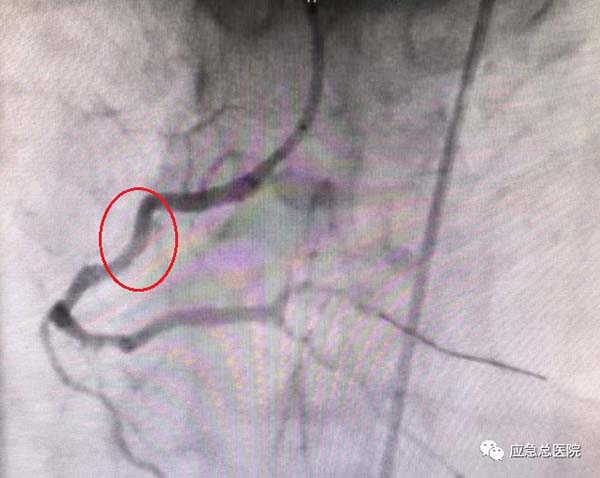

介入手术后

考虑到患者基础病多,病情复杂,治疗棘手,经过综合分析研判后,导管室范煜东主任率团队为患者实施手术。

40分钟后,成功为患者植入两枚冠脉支架,迅速开通了冠脉循环,挽救了患者的心肌,为其康复后顺利出院奠定了坚实的基础。其精湛的医术、认真负责的精神、及时的救治,让患者和家人由衷称赞。于是便出现了文中开头的一幕。